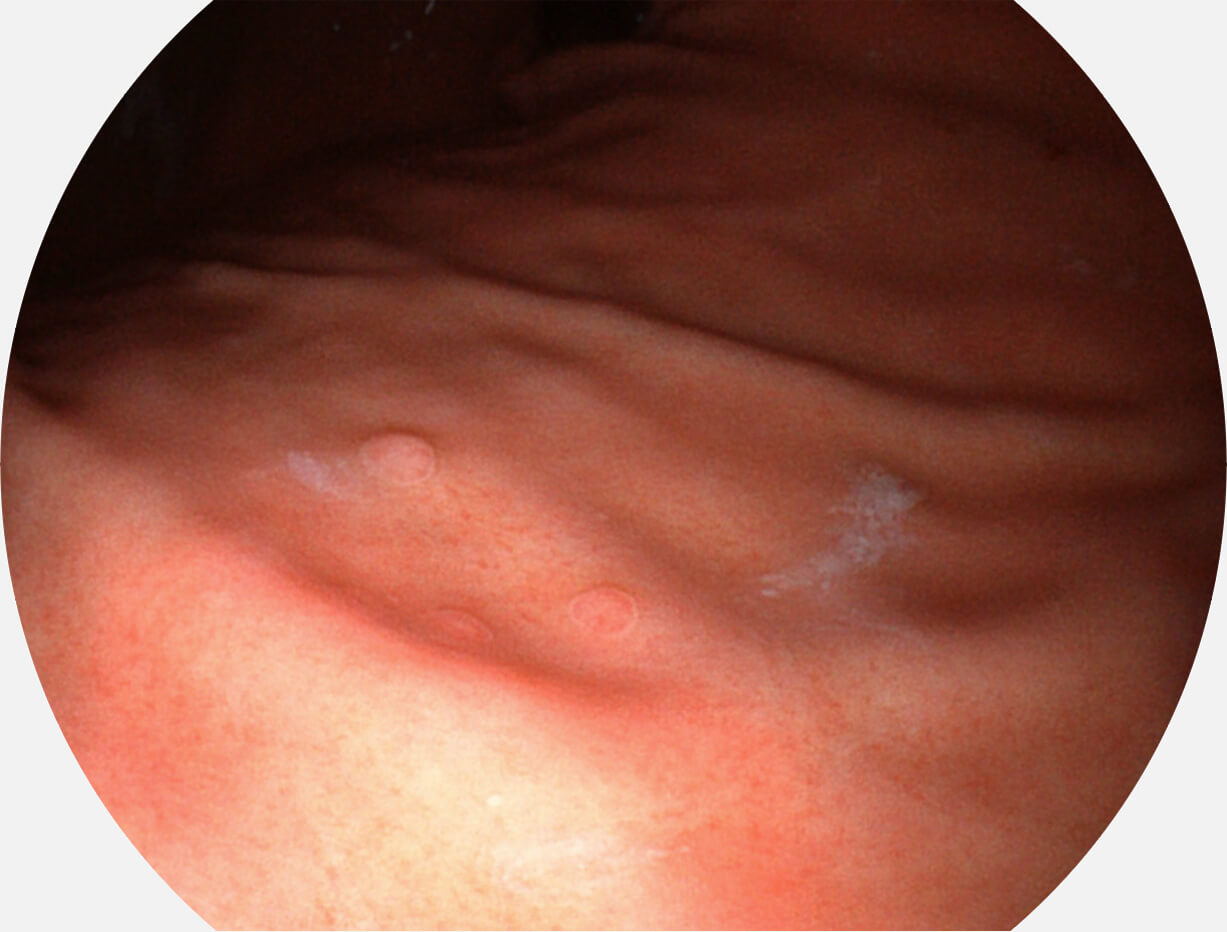

白光图像

VIST图像